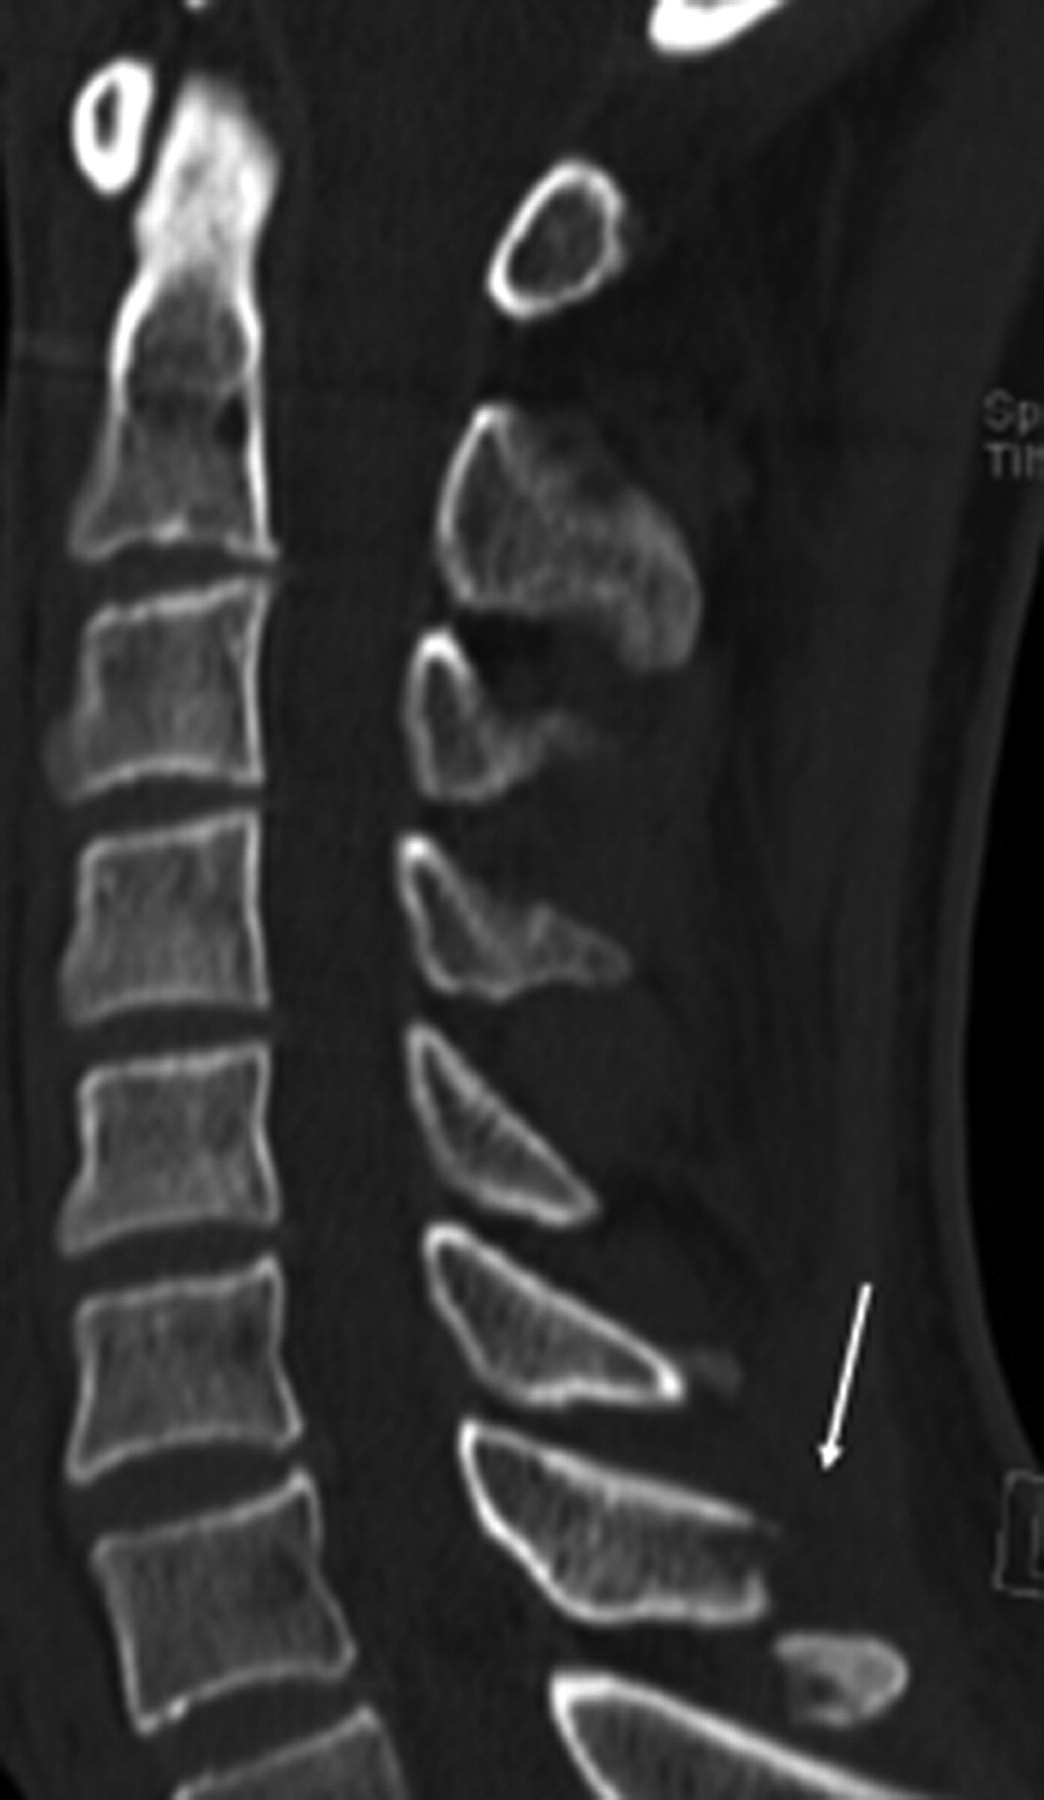

Of 191 patients, MDCT showed 18 patients with fracture(s) (9.4%), 3 in the standard-dose examinations and 15 in the low-dose examinations, with 4 fractures in the high-kilovolt group and 11 in the low-kilovolt group. Of these 18 fractures, 14 were unstable fractures (77.7%). Most fractures were situated at the C1–C2 level (n = 12): a large number of fractures at the base of the dens axis alone (n = 4; Fig 1) or in combination with other fractures (n = 2) at the level of C1 or C2 (Fig 2); 3 bilateral fractures of the arcus of C1 and/or C2; 2 pathologic fractures at the level of C2 (Fig 3); and 1 Hangman fracture. Two patients had an unstable burst fracture of a vertebral body (Fig 4). In 3 fractures, there was associated subluxation. Stable fractures were fractures of a spinous (n = 2; Fig 5 or of a lateral process (n = 2). The 2 experienced radiologists (R1 and R2) correctly identified all of the fractures in the first image interpretation at the moment of the presentation of the patient. The resident with 1 year of experience in CT (R3) also correctly identified all of the fractures. The first-year resident with no CT experience (R4) missed 3 fractures: 1 unstable fracture at the base of the dens axis (C2) and 2 stable fractures, 1 of a spinous and 1 of a transverse process. In 4 patients, standard radiography of the cervical spine at the moment of the presentation of the patient was interpreted as negative, whereby MDCT clearly depicted a fracture, 2 of them unstable fractures at the base of the dens axis (Fig 6).

A 39-year-old man with hyperextension trauma of the cervical spine. Sagittal 2.5-mm image shows fracture of the spinous process of C7 (arrow). Calculated effective dose of low-dose 6-MDCT examination (110 kV and 56 mAs) is 0.78 mSv.